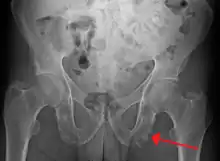

Enthesopathy of the pelvis likely due to ankylosing spondylitis

An enthesopathy refers to a disorder involving the attachment of a tendon or ligament to a bone.[1] This site of attachment is known as the enthesis (pl. entheses). If the condition is known to be inflammatory, it can more precisely be called an enthesitis.